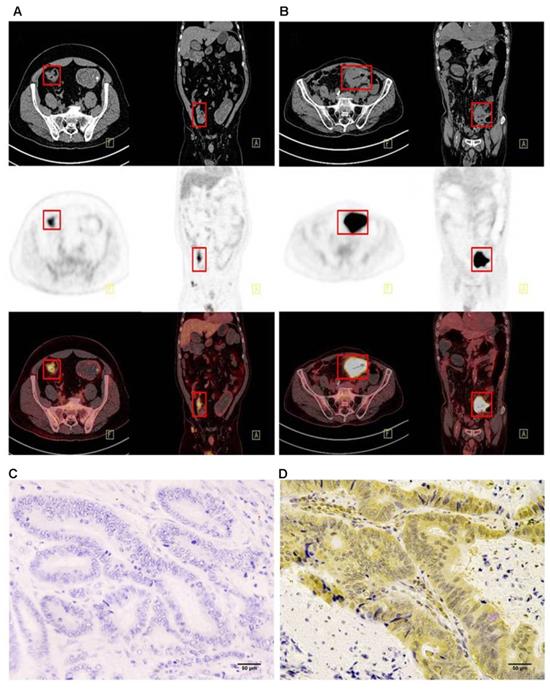

Figure 2

Representative imaging of immunohistochemical staining with PD-L1 expression and 18F-FDG PET with high 18F-FDG (B) (D) and low 18F-FDG accumulation (A) (C): The maximum standardised uptake values were 9.09 (A) and 39.01 (B) (red frame). The immunostaining pattern of PD-L1 was membrane, and the cases with scoring of 2 (C) and scoring of 6 (D) were presented. PD-L1, programmed death ligand-1; 18F-FDG, 2-Deoxy-2-[fluorine-18] fluoro-D-glucose; PET, positron emission tomography.

Immunohistochemistry was performed using the main sites of 65 CRC. A representative image of PD-L1 high and low expressions are shown in Figure 2. PD-L1 immunostaining is mainly localized in the plasma membrane of cancer cells30. The high PD-L1 expression rate was 68% (44/65). The relationship between PD-L1 and patient clinicopathological features is shown in Table 1. High expression of PD-L1 was significantly associated with tumor size (P=0.001), lymph node metastasis (P=0.034), tumor TNM stage (P=0.017), and tumor vascular invasion (P=0.020). And based on the comparison of SUVmax, MTV3.0 and TLG3.0 expressed by PD-L1, SUVmax, MTV3.0 and TLG3.0 values were significantly higher in patients with CRC with high PD-L1 expression than those with low expression; the difference was statistically significant (Figure 3).